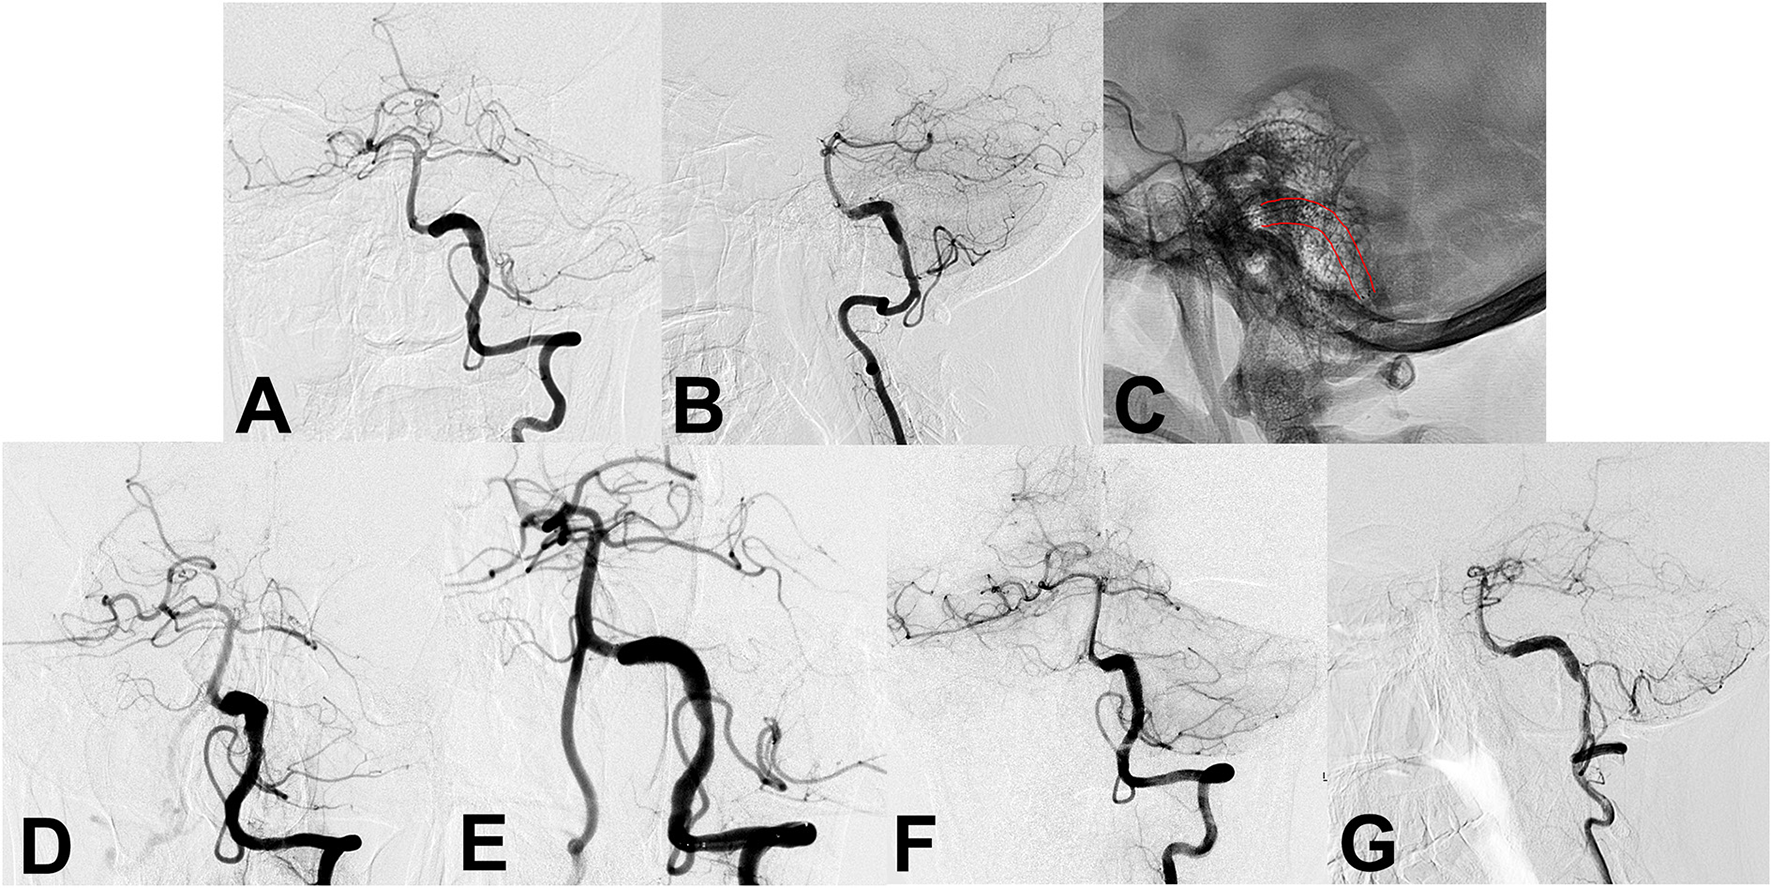

Figure 1

(A,B) Preoperative angiography shows an unruptured vertebral artery fusiform aneurysm. (C) Intraoperative angiography shows the successful placement of a single conventional stent (lines). (D,E) Angiography immediately after stent placement showed residual flow inside the aneurysm. (F,G) Follow-up angiography 6 months after the procedure continued to show residual aneurysm.